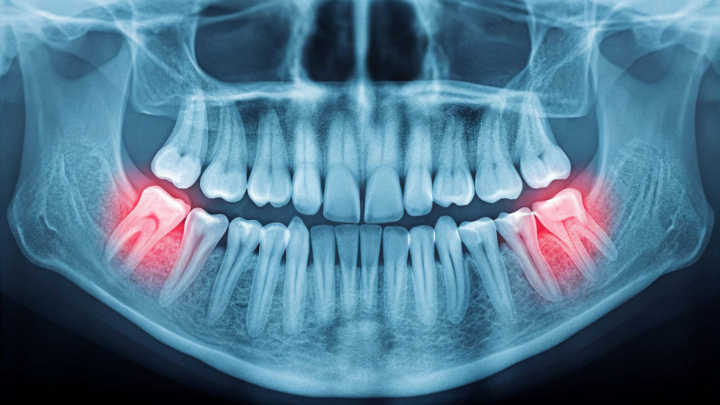

親知らずが顎の骨の中に留まり、外から確認できないままの状態もあります。これは埋伏歯と呼ばれ、レントゲン検査で見つかることが一般的です。

痛みや腫れなどの症状がなければ経過観察となることもありますが、周囲の歯に影響を与える位置にある場合や、内部で炎症が起こる場合には注意が必要です。